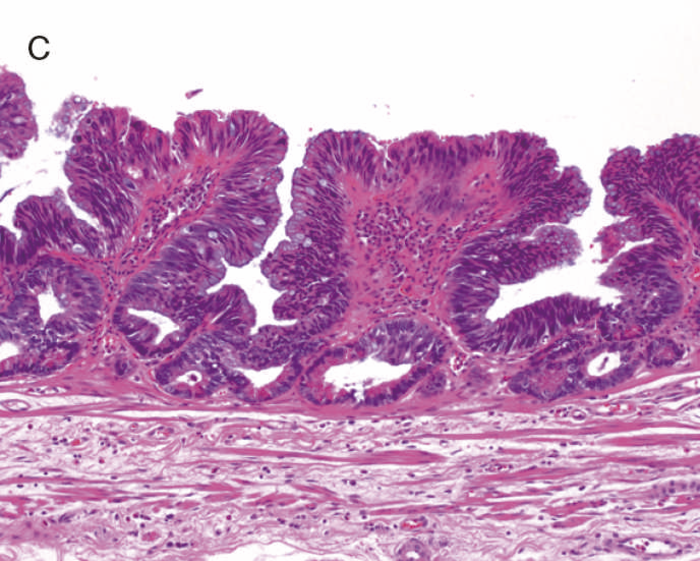

通常の散発性進行大腸癌の多くは潰瘍限局型(2型)であるが,UC関連進行大腸癌は潰瘍浸潤型(3型),びまん浸潤型(4型)や分類不能型(5型)が多いとされる(図7)。初期病変であるdysplasiaの肉眼形態に関しては,混合型を含む約70%の症例が何らかの隆起成分を有することが報告されている1,2)。ただ同じ隆起といっても,UC関連大腸腫瘍の多くは境界不明瞭な丈の低い顆粒状・結節状・不整扁平隆起を呈する一方で,散発性腫瘍は有茎性もしくは亜有茎性病変,境界や立ち上がりが明瞭な病変であることが多く,詳細な肉眼形態の観察は両者の鑑別に重要である。二番目に多い肉眼形態は平坦型であり,全体の約30%を占める1,2)。散発性大腸腫瘍の平坦型は極めて頻度が低いことから,平坦型成分の存在もdysplasiaの特徴といえる(図8)。

図8 Dysplasiaの代表的な肉眼像(平坦型)

- 直腸部の赤色点線部より肛門側(左側)に拡がるdysplasia(平坦型)を認める。

- 同平坦部では組織学的に高分化管状腺癌(粘膜内癌)を認めた。